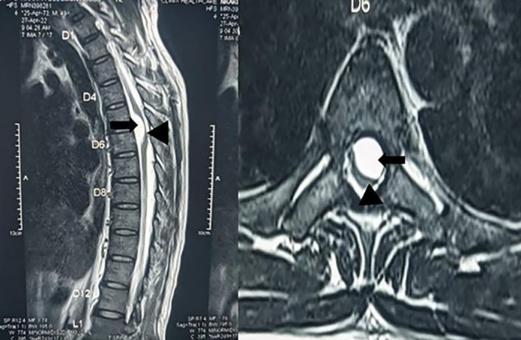

该患者没有并发症,术后MRI显示蛛网膜囊肿完全切除,脊髓再次扩张以填充椎管横截面,伴有脊髓水肿和少量硬膜外脑脊液收集。(图4)

图4、胸椎磁共振成像矢状面(左)和轴面(右)显示蛛网膜囊肿完全切除,脊髓再扩张(白色箭头),少量硬膜外脑脊液收集(黑色箭头),以及相关的脊髓水肿(黑色箭头)